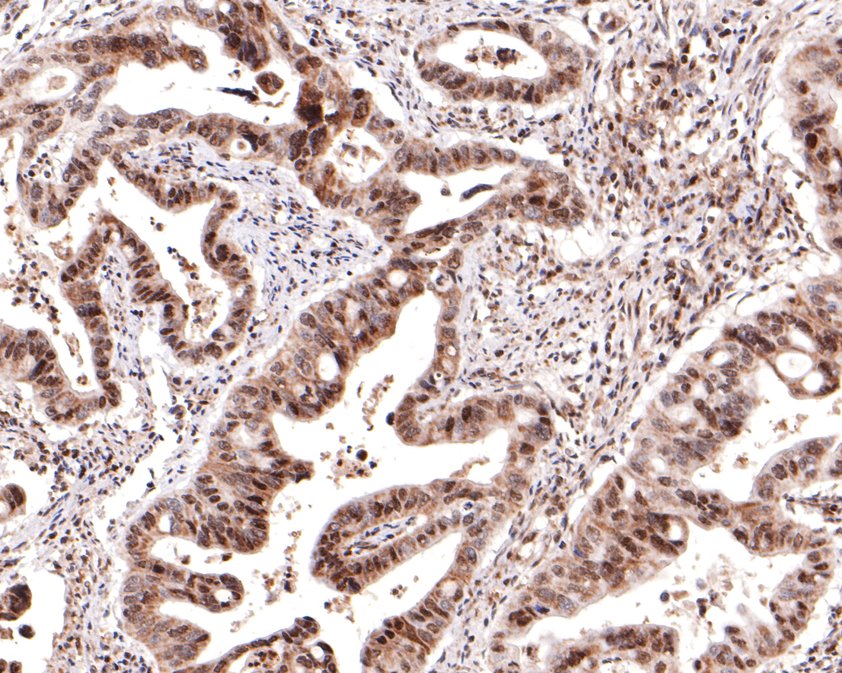

Immunohistochemical analysis of paraffin-embedded human cervix carcinoma tissue with Rabbit anti-Caspase-9 antibody (HA750062) at 1/400 dilution.

The section was pre-treated using heat mediated antigen retrieval with sodium citrate buffer (pH 6.0) (high pressure) for 2 minutes. The tissues were blocked in 1% BSA for 20 minutes at room temperature, washed with ddH2O and PBS, and then probed with the primary antibody (HA750062) at 1/400 dilution for 1 hour at room temperature. The detection was performed using an HRP conjugated compact polymer system. DAB was used as the chromogen. Tissues were counterstained with hematoxylin and mounted with DPX.